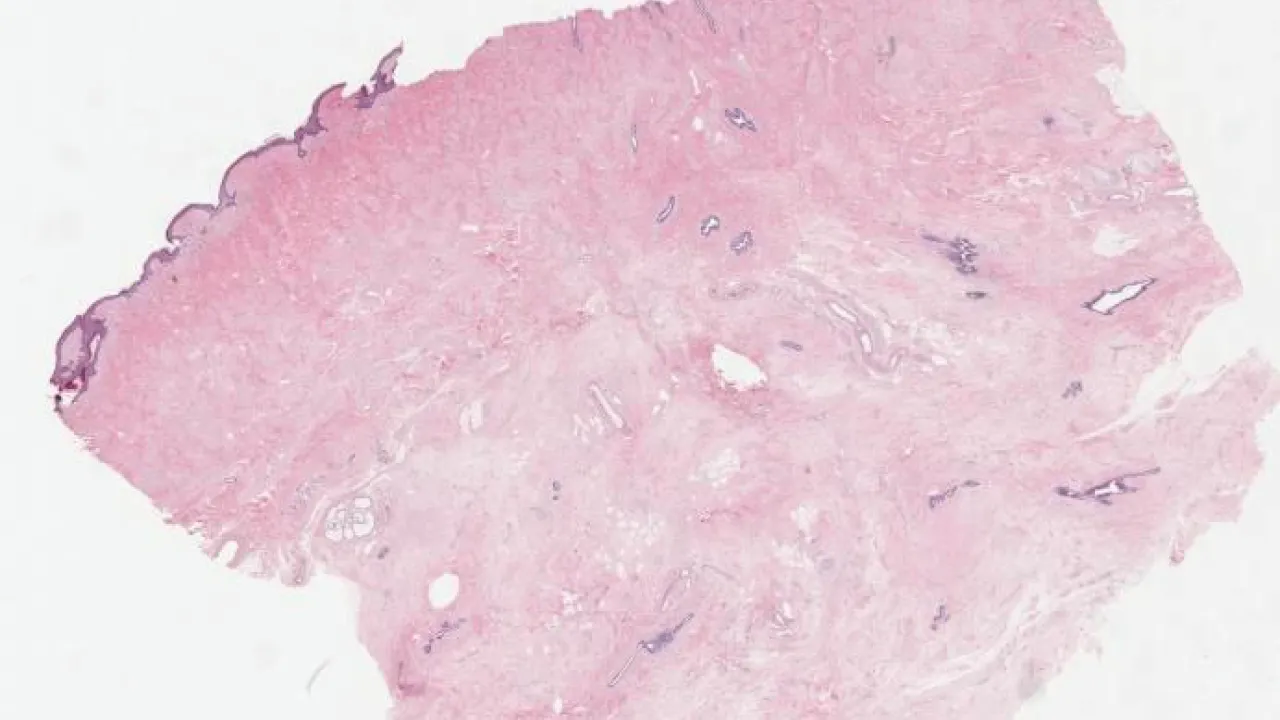

Colon, collagenous colitis